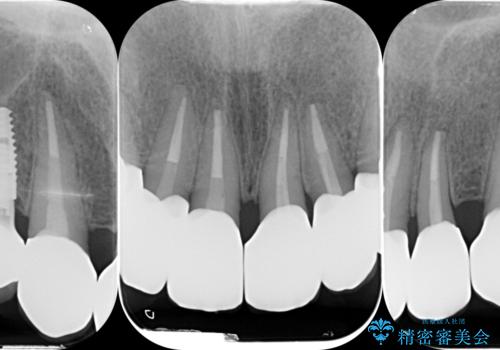

歯周組織検査を行うと歯ぐきからは容易に出血し、X線検査より歯とセラミッククラウンの適合が悪い(ピッタリと合っていない)状態が示唆され、歯ぐきの炎症を惹起している状態でした。

セラミッククラウンを除去し仮歯を装着し、歯周外科手術を行い歯ぐきの状態を改善したのち、適合の良いセラミッククラウンを再作製をする治療計画としました。